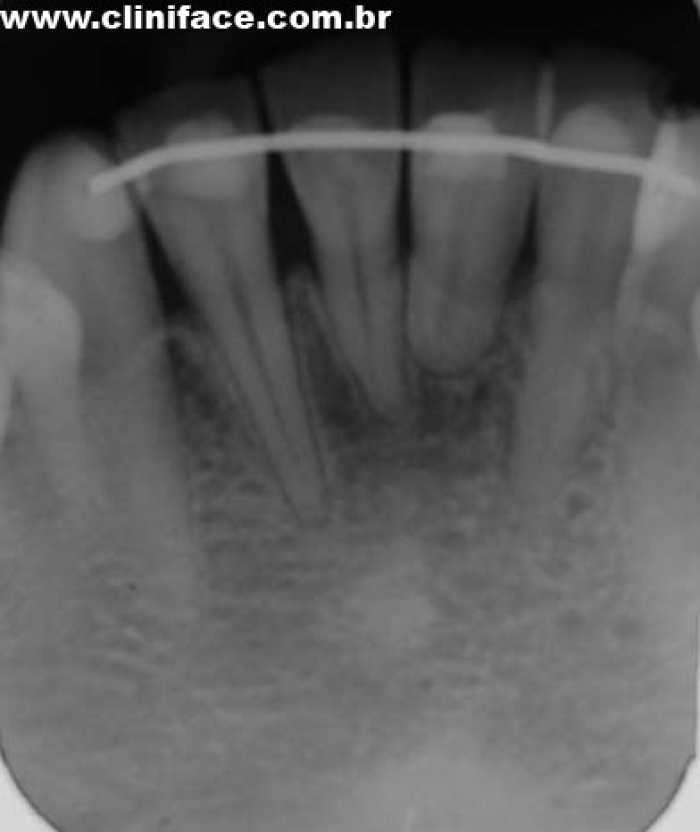

Imagens do elemento 31, apresentando extensa reabsorção radicular externa

Rx inicial